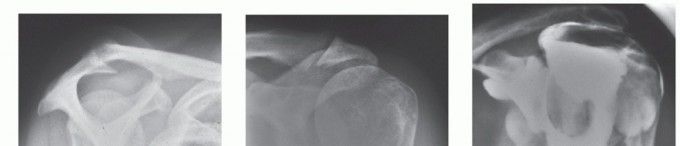

DEFINITION Proximal humerus fractures may involve the surgical neck, the greater tuberosity, and/or the lesse…

DEFINITION Proximal humerus fractures are defined as those of the proximal portion of the humerus involving t…